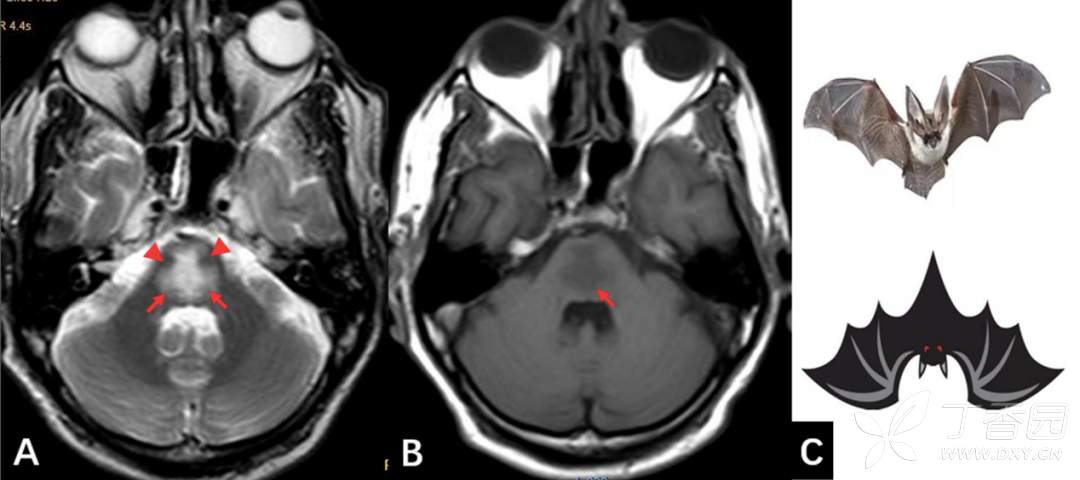

图 8-1. 脑桥中央髓鞘溶解症(CPM)

A. 轴位 T2WI 扫描示脑桥中央片状稍高异常信号,呈「蝙蝠翼」样改变(红色箭),而皮质脊髓束保持完整(红色箭头);B. 轴位 T1WI 示脑桥中央片状稍低信号(红色箭头);C. 蝙蝠翼示意图